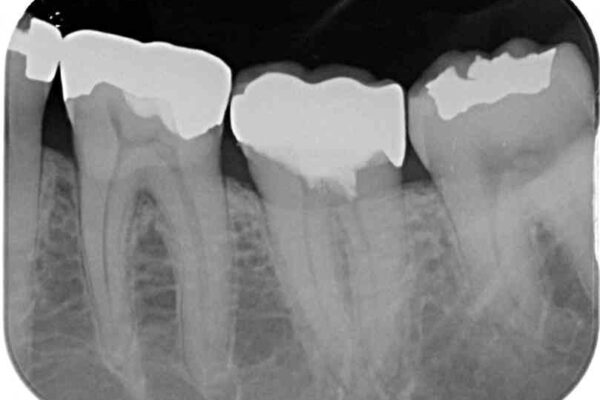

診査をしたところ、神経組織に影響を及ぼすような大きな虫歯があることが分かりました。

虫歯が歯髄腔(神経の部屋)に達している可能性が非常に高かったため、炎症を起こしている神経組織を部分的に切除し、歯根部分の神経組織を保存する治療法が望ましいと考えられました。

虫歯は深くまで進行しており、歯冠部の神経から出血が認められました。神経を部分的に除去したところ出血が治まったので、生体親和性の非常に高いセメントにて充填し、仮封をしました。

治療前

• 治療をしても違和感の続く奥歯 神経を極力残した虫歯治療 治療前画像